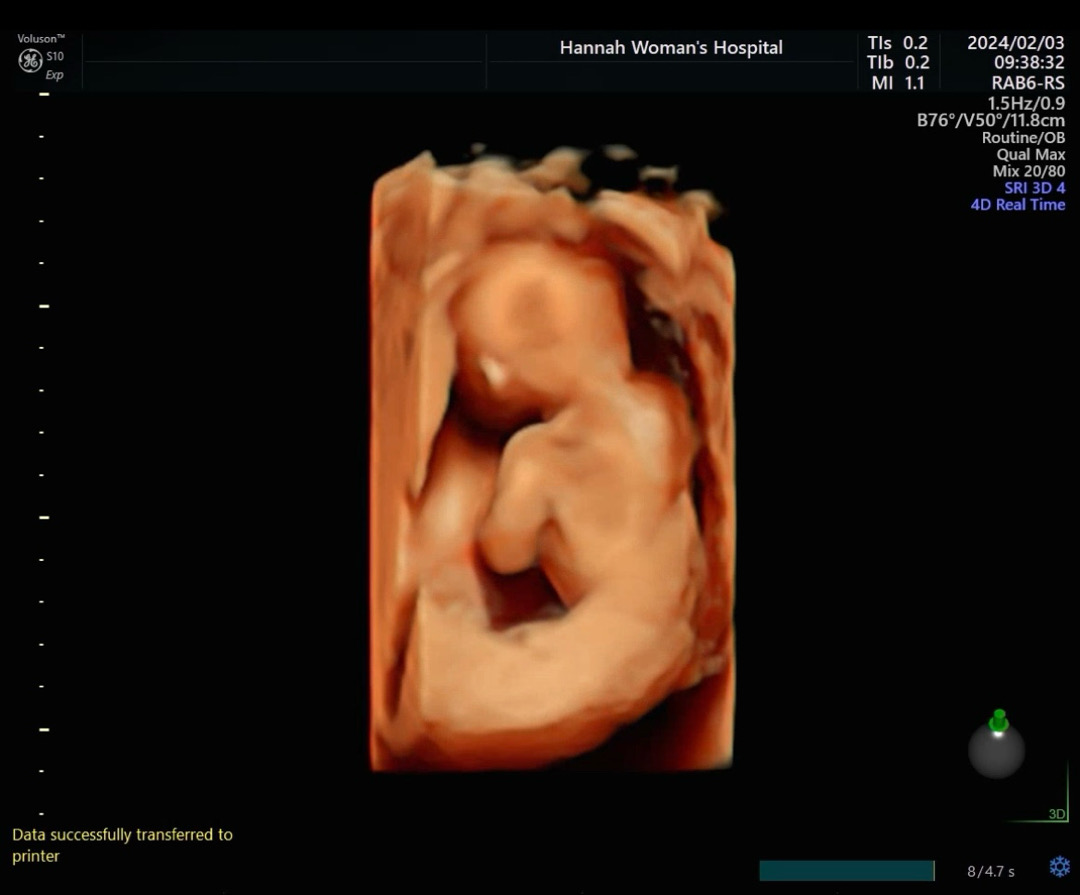

17주차 너무 귀여운 뒷모습💙💙

오늘 촘파 보고 왔는데 이런 깜찍한 뒷모습을 보고왔네요! 귀도 보여주고😊 초기때부터 여러걱정들 많이 하면서 지내왔는데 이제 뭔가 조금 안심이 되면서 잘커준모습에 눈물이나네요🥹 빨리 태동도 느껴봤으면~ 기대중입니다!!💙